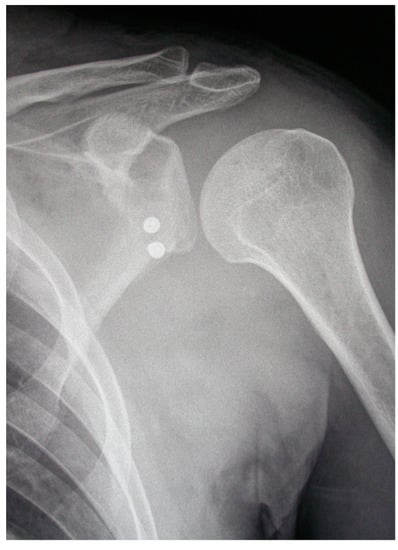

- The pectoralis minor was released, and a fresh portal was established with a needle over the coracoid, to insert the drill holes, at the junction of the lateral 2/3 and the medial 1/3. Two Kirschner wires through the coracoid were passed. The drill guide was removed. The holes were tapped, and the top hats were inserted into the fragment using a flexible Chia wire. The osteotomy was completed (Figure 2). The bone fragment was secured thought a coracoid screw passed over the Chia wire, using a double cannula.

- The graft was positioned on the anterior glenoid neck with the switching stick through the posterior portal (Figure 3).

- The graft was fixed. Two holes were made through the coracoid and the glenoid using the double cannula. Graft trimming was performed with the burr (Figure 4).